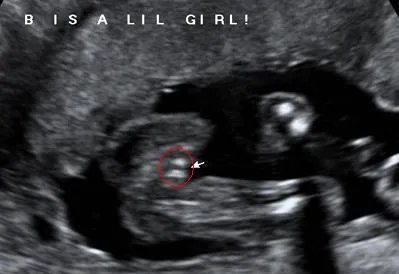

首先是女宝宝的, “三线” 是一个明显的标记: